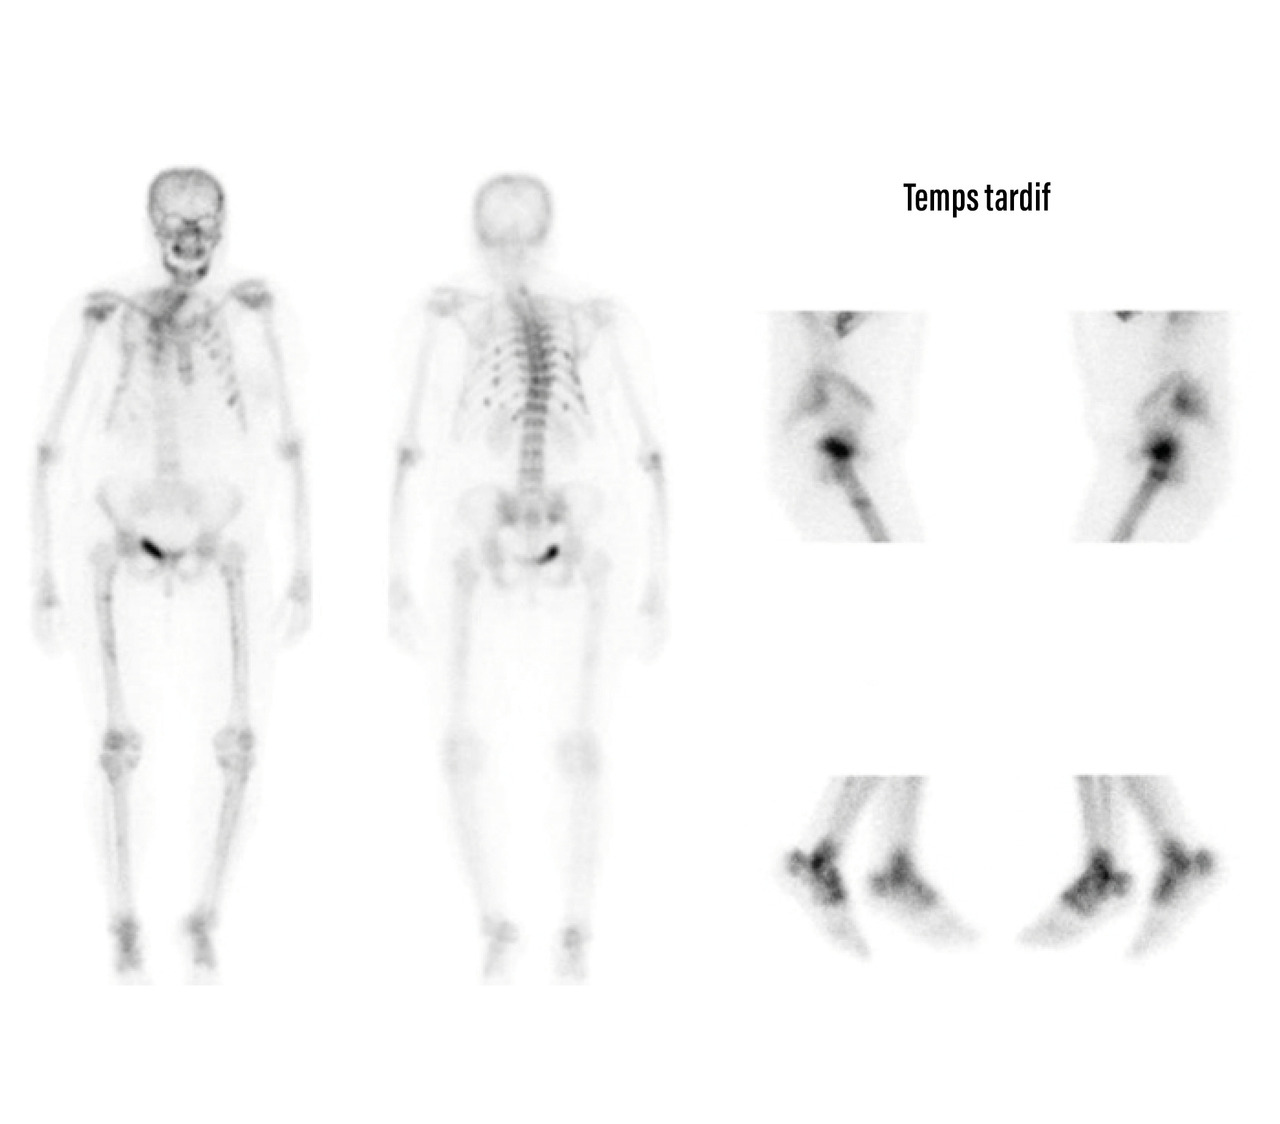

Scintigraphie osseuse au technétium marqué (Tc- 99m)

Cet examen peut mettre en évidence un ou plusieurs foyers d’hyperfixation (fig. 5).